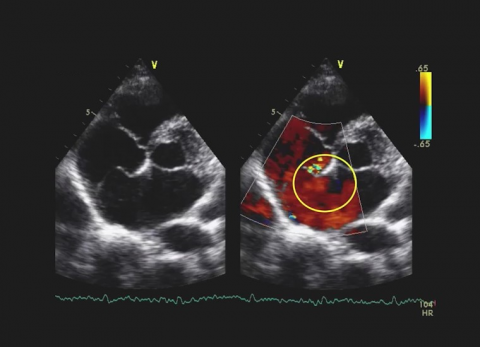

Wideo Pułapki Echokardiograficzne. Przypadek 38

dr n. med. Barbara LichodziejewskaZatoka wieńcowa, zastawka trójdzielna, prawa komora.